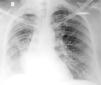

Case reportA 48-year old lady presented to the Chest Clinic with complaints of dry cough of six months duration. There was no history of fever, dyspnea, chest pain, wheeze or hemoptysis. She denied any addictions. Physical examination was unremarkable. Pulse oximetric saturation was 99% on room air. A chest radiograph was suggestive of volume loss in the right hemithorax (Fig. 1). Computed tomography (CT) of the thorax showed a low attenuation tumor in the right main bronchus suggestive of a fat containing lesion (Fig. 2). FB revealed the presence of a yellowish tumor with a smooth external surface causing near total occlusion of the right main bronchus (Fig. 3). The right upper lobe bronchus was not visualized and the bronchoscope could not be advanced into the right main bronchus. The patient was advised to have a rigid bronchoscopic removal of the tumor however she was not willing to have a general anesthesia.